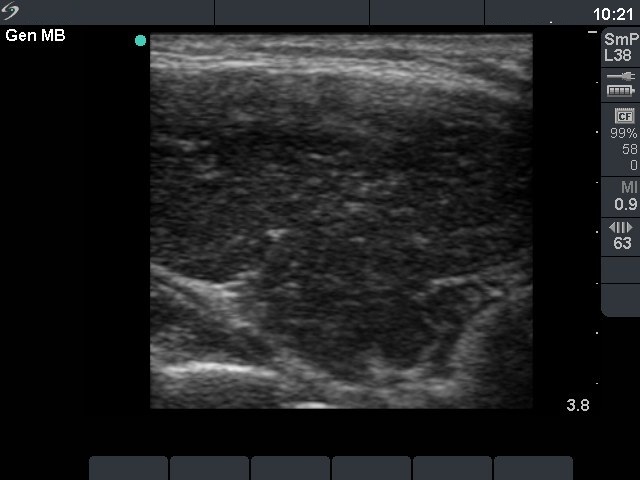

First investigation 6 months after delivery (first and second rows of images)

Clinical presentation: a 22-year-old woman was referred for an evaluation of a newly discovered hypothyroidism. She had fatigue and hair loss. She has been delivered 6 months before present investigation.

Ultrasonography: the thyroids were hypoechogenic without any nodule. The vascularization was increased.Cytology resulted in Hashimoto's thyroiditis.

Clinical diagnosis: hypothyroidism, post partum thyroiditis.